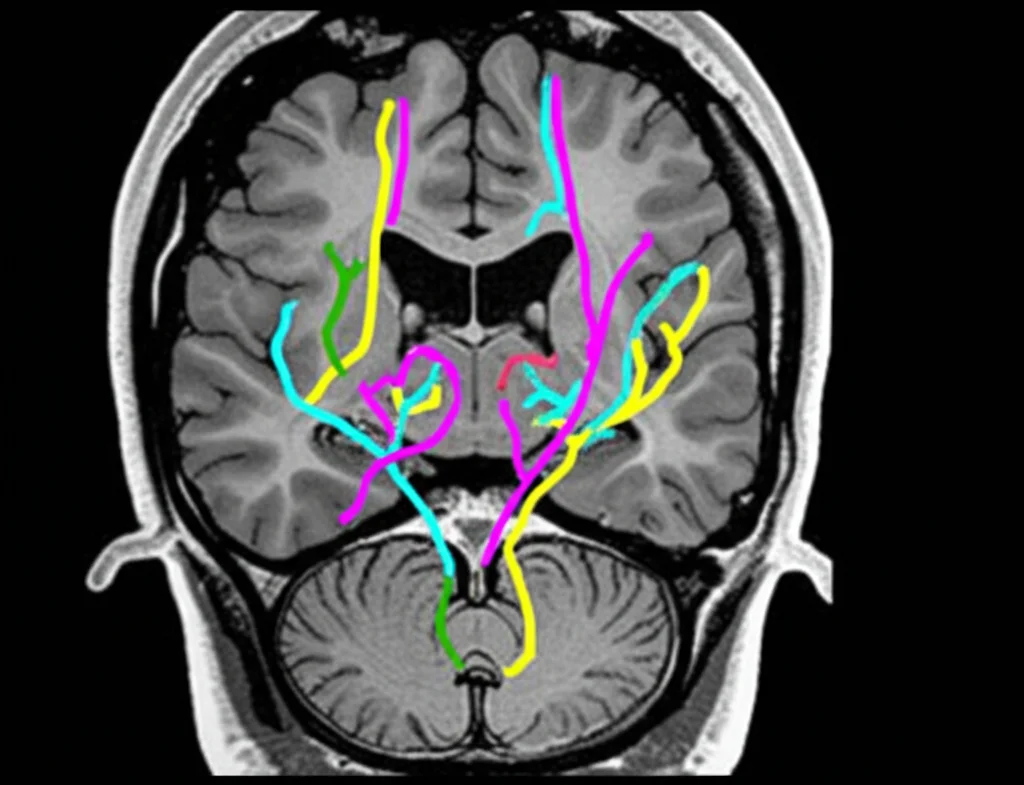

I movimenti oculari sono controllati da circuiti cerebrali complessi, molti dei quali sono colpiti dal Parkinson e da altre sindromi parkinsoniane, come la Paralisi Sopranucleare Progressiva (PSP). Nella PSP, ad esempio, i problemi nei movimenti oculari verticali (guardare su e giù) sono così caratteristici da essere inclusi nei criteri diagnostici.

Nel Parkinson “classico”, i problemi oculari possono essere più sottili, ma ci sono. Spesso si notano saccadi (i movimenti rapidi dell’occhio per spostare lo sguardo) un po’ più lente a partire, leggermente “corte” (ipometriche), e una difficoltà a sopprimere i movimenti riflessi. La video-oculografia (VOG) è uno strumento fantastico perché permette di misurare questi movimenti con grande precisione, molto più di quanto si possa fare a occhio nudo durante una visita. È non invasiva e relativamente semplice da eseguire.